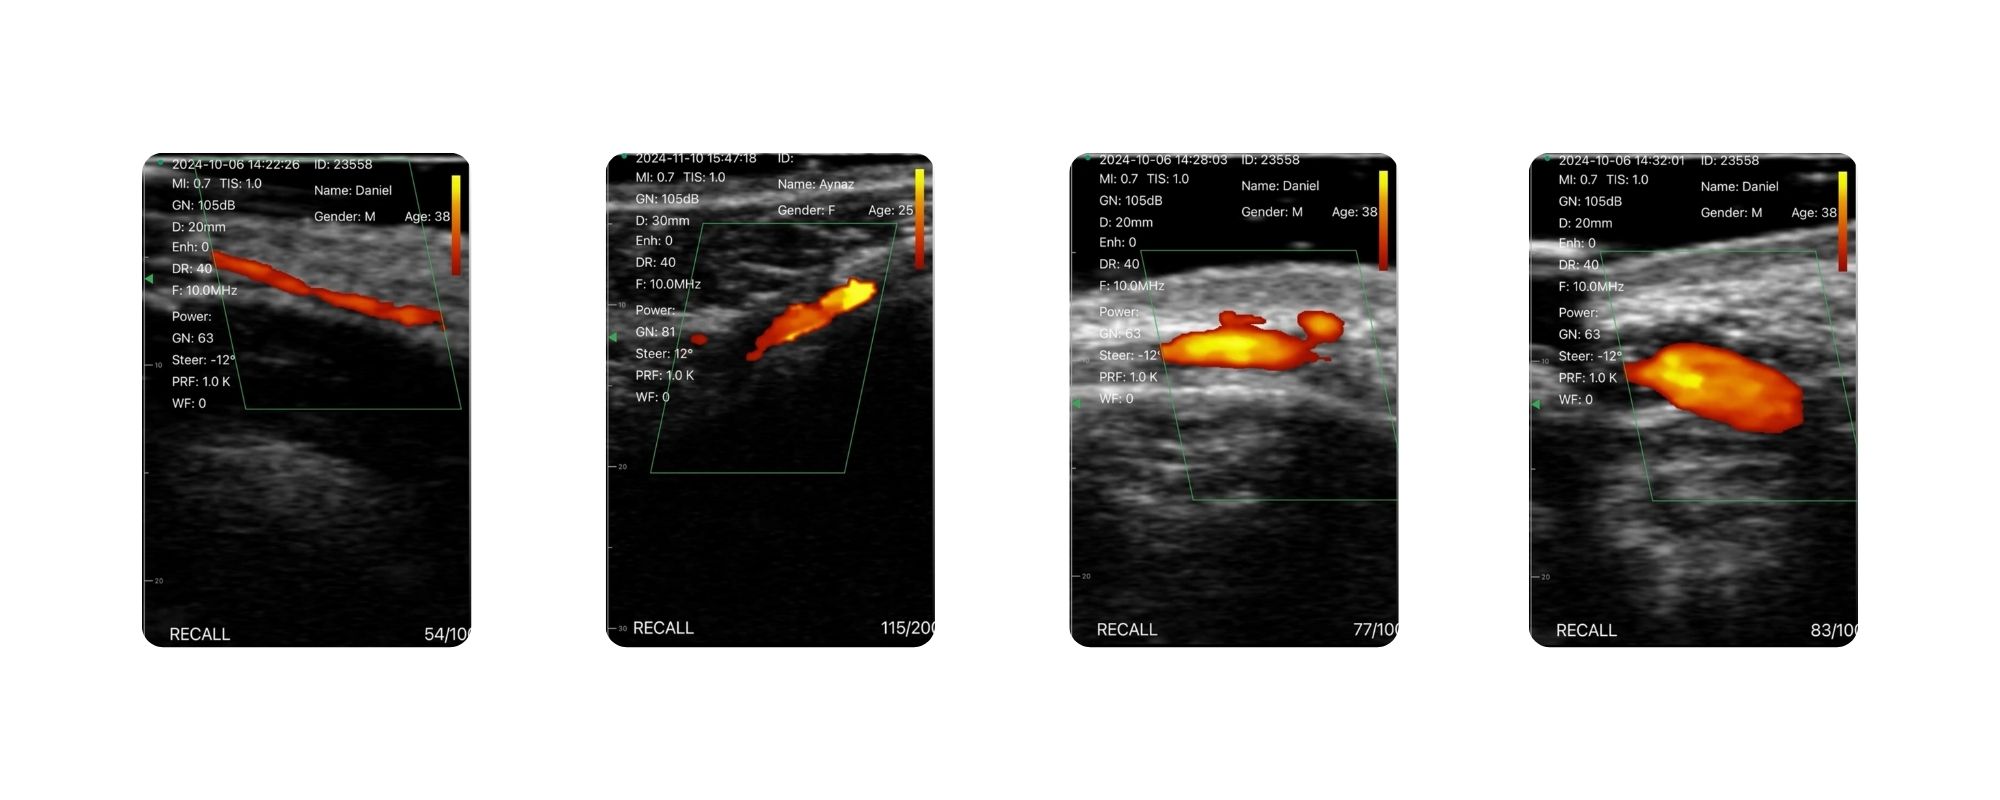

یکی از مهمترین ویژگیهای این دستگاه با توجه به امکان پاور داپلر، توانایی شناسایی دقیق عروق صورت، رگهای باریک و مسیر آنها است. با مشاهده مسیر عروق در زمان واقعی، پزشک میتواند از فشرده شدن یا مسدود شدن رگها جلوگیری کرده و مطمئن شود که تزریق ژل یا بوتاکس به محل مناسب و با عمق درست انجام میشود.

سونواستار هندهلد در حالت پاور داپلر برای شناسایی عروق باریک بدون ایجاد مشکل گرمایی عمل میکند، در حالی که برخی برندها به دلیل گرمای بیش از حد به طور خودکار خاموش میشوند. تمامی مدهای تصویربرداری در این دستگاه به صورت رایگان و دائمی فعال هستند و برخلاف مدلهایی که نیاز به شارژ ماهانه دارند، هزینههای اضافی مطب را افزایش نمیدهند.

تمام مدهای تصویربرداری مورد نیاز در زیبایی B، B/M ، Color، PW و PDI، در این دستگاه فعال هستند و مجموعهای کامل از اطلاعات را برای تصمیمگیری بالینی فراهم میکنند. رنگ آبی سر دستگاه نیز ظاهری حرفهای و مناسب محیطهای کلینیکی دارد.